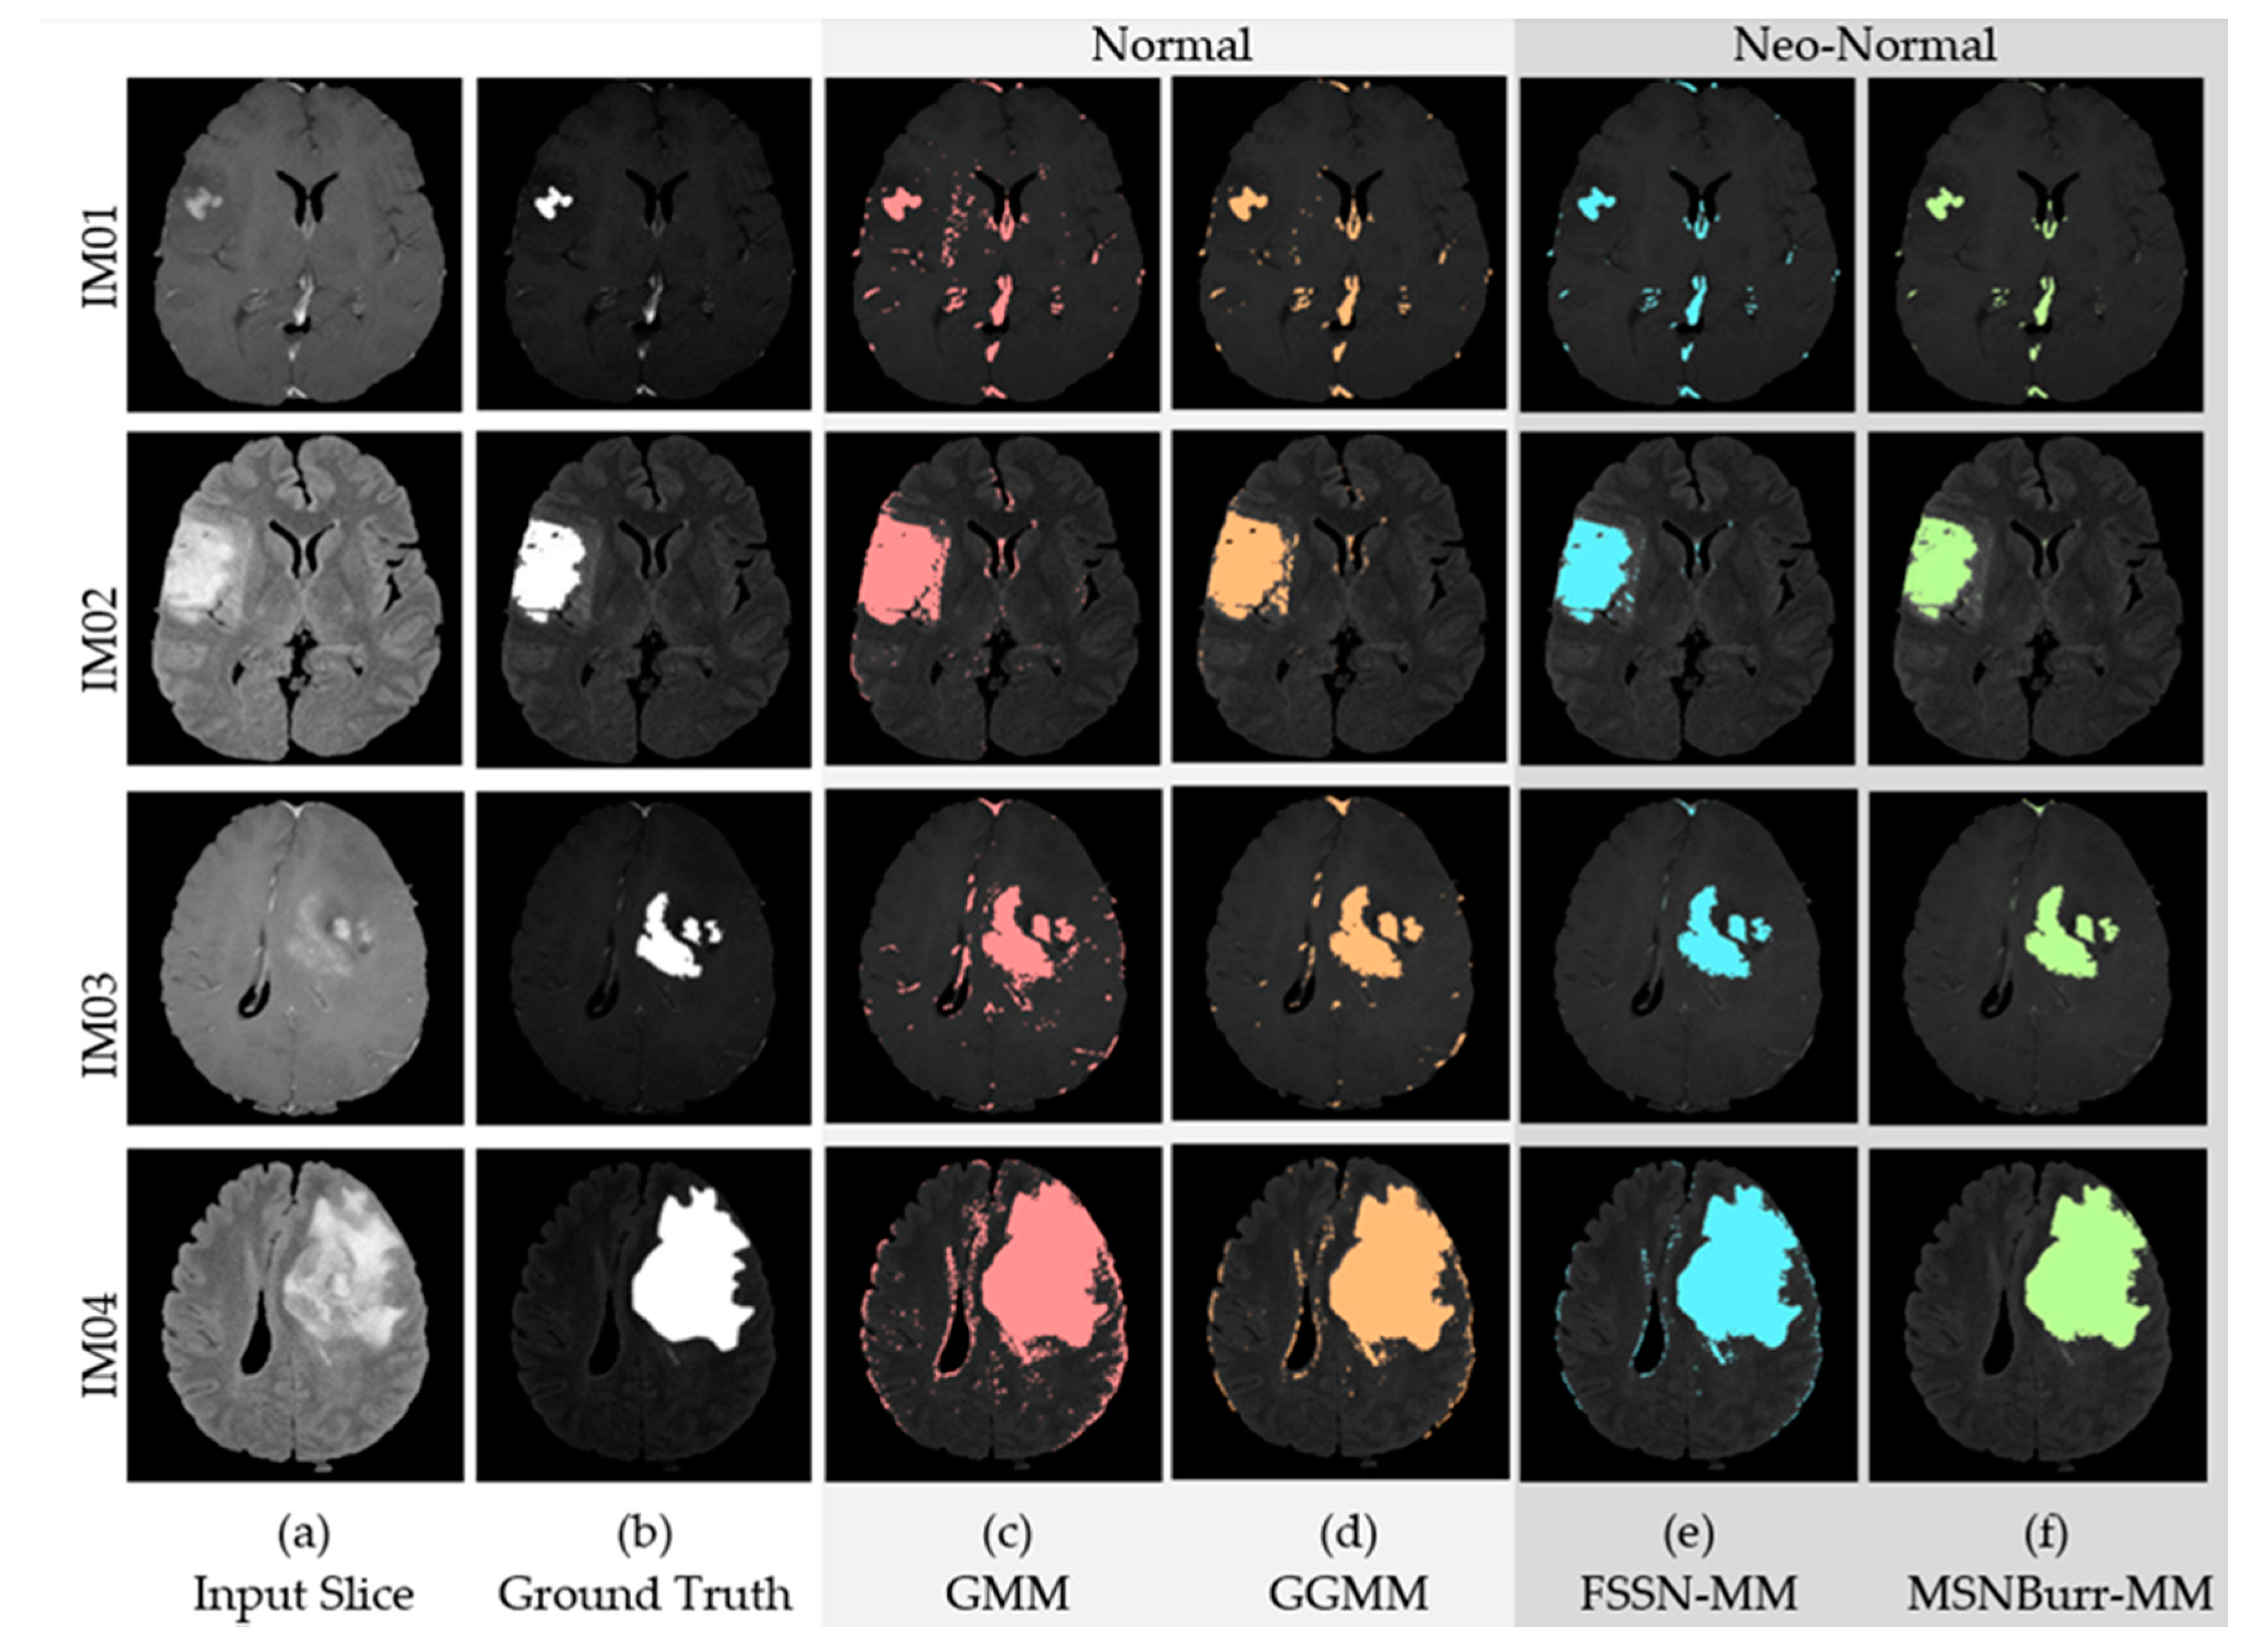

5.2. Application for MRI-Based Brain Tumor

| Algorithm | Dataset | Number of Clusters (K) | |||||||

|---|---|---|---|---|---|---|---|---|---|

| 3 | 4 | 5 | 6 | 7 | 8 | 9 | |||

| Normal | GMM | IM01 | 0.5498 | 0.3488 | 0.539 | 0.4553 | 0.6949 * | 0.6936 | 0.654 |

| IM02 | 0.904 | 0.9133 * | 0.748 | 0.6909 | 0.758 | 0.795 | 0.748 | ||

| IM03 | 0.7924 | 0.803 | 0.8356 * | 0.8034 | 0.7654 | 0.7497 | 0.7138 | ||

| IM04 | 0.8875 | 0.9275 * | 0.8764 | 0.8759 | 0.8437 | 0.7868 | 0.7745 | ||

| GGMM | IM01 | 0.8021 | 0.8263 * | 0.7412 | 0.7406 | 0.6824 | 0.6211 | 0.5488 | |

| IM02 | 0.7682 | 0.8487 | 0.8935 * | 0.8204 | 0.7581 | 0.6328 | 0.7004 | ||

| IM03 | 0.9002 * | 0.8955 | 0.7324 | 0.7101 | 0.6048 | 0.5545 | 0.6266 | ||

| IM04 | 0.8333 | 0.8859 * | 0.8479 | 0.8022 | 0.7643 | 0.7614 | 0.7321 | ||

| Neo-Normal | FSSN-MM | IM01 | 0.8725 * | 0.6412 | 0.6752 | 0.6351 | 0.5897 | 0.6325 | 0.6606 |

| IM02 | 0.8109 | 0.8636 * | 0.8464 | 0.812 | 0.8467 | 0.7929 | 0.8292 | ||

| IM03 | 0.9145 * | 0.8014 | 0.7512 | 0.7049 | 0.6854 | 0.7046 | 0.6699 | ||

| IM04 | 0.8347 | 0.9010 * | 0.9009 | 0.8794 | 0.8695 | 0.8529 | 0.7558 | ||

| MSNBurr-MM | IM01 | 0.9300 * | 0.8349 | 0.7412 | 0.7218 | 0.714 | 0.7331 | 0.7435 | |

| IM02 | 0.8428 | 0.9119 * | 0.9106 | 0.7729 | 0.7322 | 0.6731 | 0.7091 | ||

| IM03 | 0.9157 * | 0.8014 | 0.7491 | 0.7072 | 0.6938 | 0.6931 | 0.6912 | ||

| IM04 | 0.8364 | 0.9230 * | 0.8647 | 0.8009 | 0.801 | 0.7647 | 0.7577 | ||